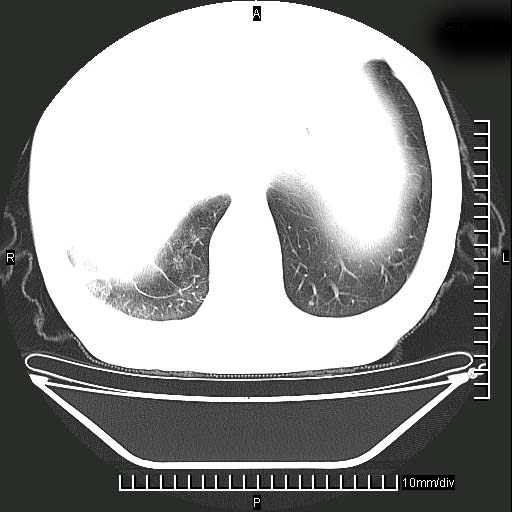

既往肺结核,近10几天,咳嗽,咳痰,右侧胸痛,疼痛较明显,右上肺斑块考虑结核灶胸膜粘连,增强,可惜动脉期没有定好,未见强化,可延迟4分后又见较明显强化,中心见低密度影,如果说结核是边缘强化,可这个灶强化的面积挺大的,让人很挠头。

延迟4分后

强化的组织可能是膨胀不全的肺组织或炎性肉芽组织。

1)两肺继发性肺结核。2)右侧胸膜增厚+少量胸腔积液。